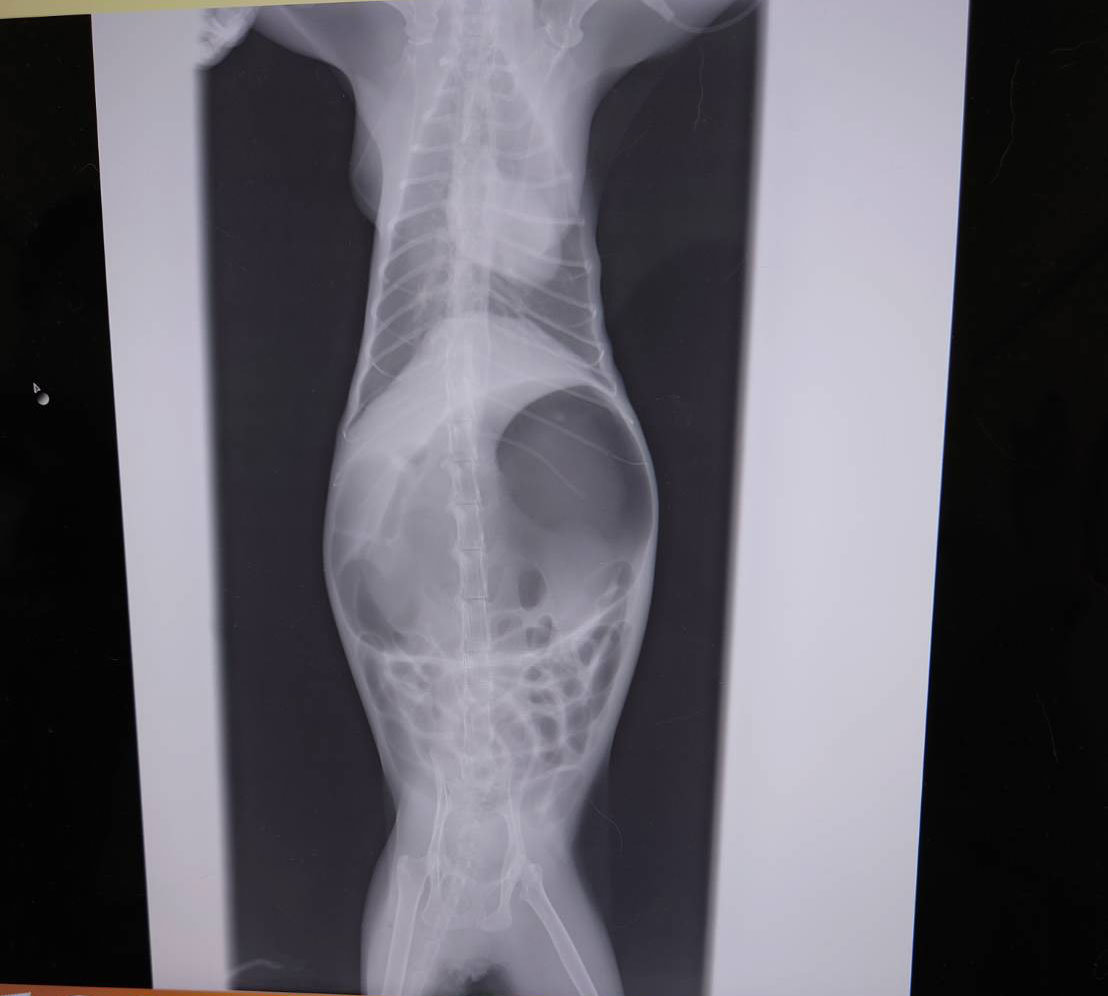

輪島で保護された臆病なキリ。体調不良が続き病院を受診したところ、膵炎でした。膵炎による食欲不振、腹部膨満などの症状も出ています。チャレンジ基金で膵炎の治療費全額を支援し、体調の回復、まだ人が怖いキリの全てを受け入れてくれる里親を見つける挑戦が始まります。